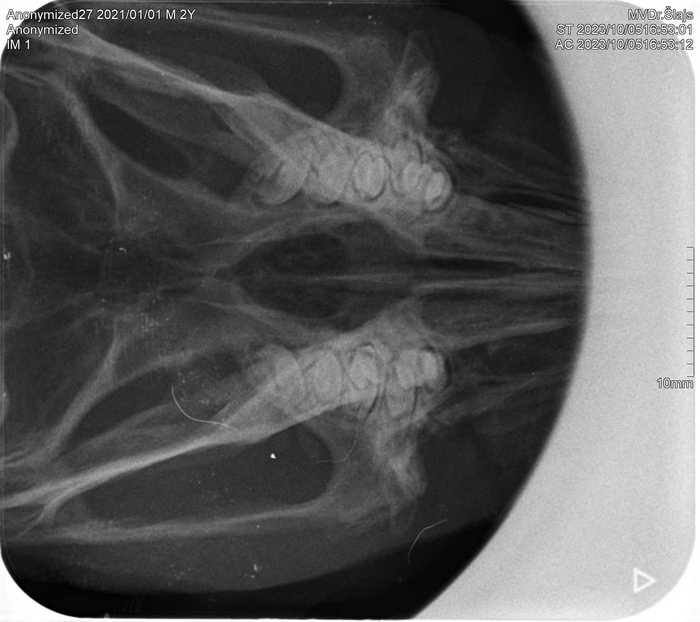

U hlodavců je RTG vyšetření nezbytné pro správné řešení syndromu onemocnění dentice (přerůstání zubů, nesprávný růst zubů). Při broušení přerostlých zubů vždy kontrolujeme i správný růst kořenů zubů právě pomocí RTG.